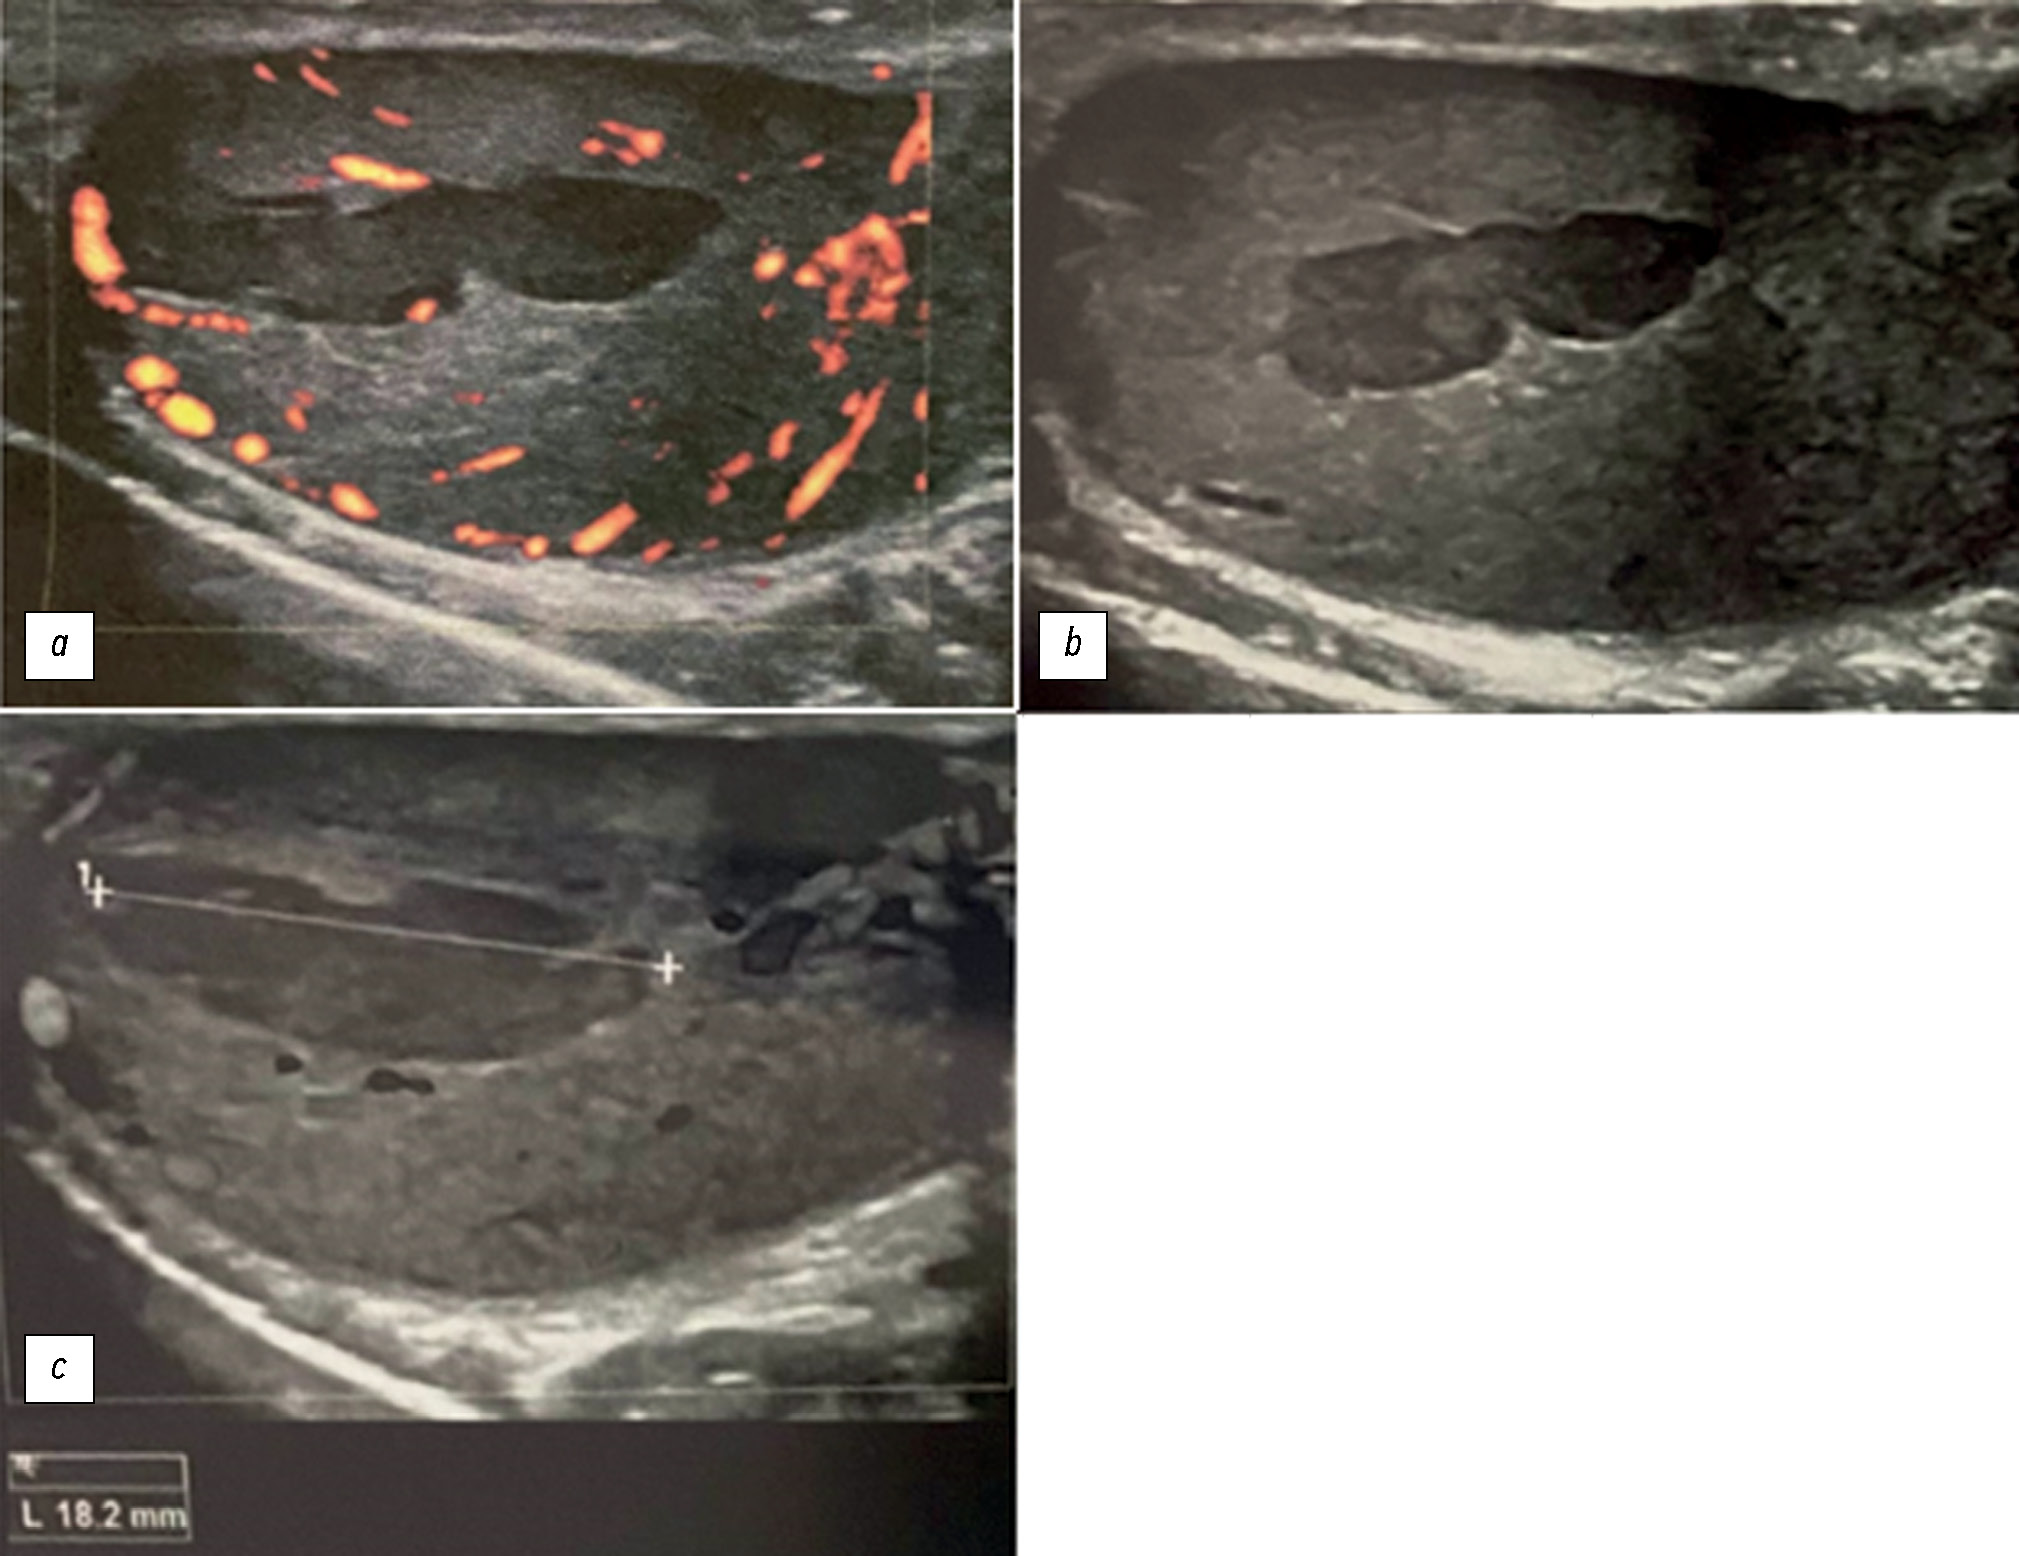

Диагноз ишемии яичек у пациента молодого возраста с жалобами на боль в мошонке слева: потенциально смертельное осложнение эпидидимита

В редких случаях острый эпидидимит сопровождается развитием ишемии и инфаркта яичек. Отличить эпидидимит от перекрута яичка по клиническим признакам и результатам визуализации достаточно непросто. В данной статье мы постарались расширить библиотеку цифровых изображений методов лучевой диагностики, используемых для быстрой и точной дифференциальной диагностики. Представленный случай подчёркивает важность комплексного лучевого обследования и необходимость междисциплинарного подхода для постановки точного диагноза. Мужчина, 24 года, обратился в больницу по поводу сильной боли в левом яичке, возникшей 2 недели назад. Со слов пациента, в течение некоторого времени у него наблюдались болезненные эякуляции, боль во время полового акта (диспареуния), покраснение/припухлость мошонки, воспаление половых органов, озноб, увеличение паховых лимфатических узлов, дизурия и боль в мошонке. По направлению уролога были проведены ультразвуковое исследование и магнитно-резонансная томография. Визуализационные исследования показали наличие ишемии левого яичка. С учётом данных анамнеза возникло подозрение на хронический орхоэпидидимит. Поскольку зона ишемии была ограниченной, пациенту не потребовалось проведения левосторонней орхидэктомии. Была назначена медикаментозная терапия. Кроме того, у пациента было выявлено левостороннее варикоцеле. Было проведено тщательное изучение изображений, полученных в различных последовательностях магнитно-резонансной томографии. В настоящей работе описан редкий случай орхоэпидидимита, который представляет собой потенциально опасное осложнение эпидидимита. Во избежание серьёзных последствий вероятность данного осложнения следует учитывать при возникновении внезапной сильной боли в мошонке. В описании данного случая представлена информация, которая позволит оптимизировать подходы к ведению пациента и избежать ненужных вмешательств.